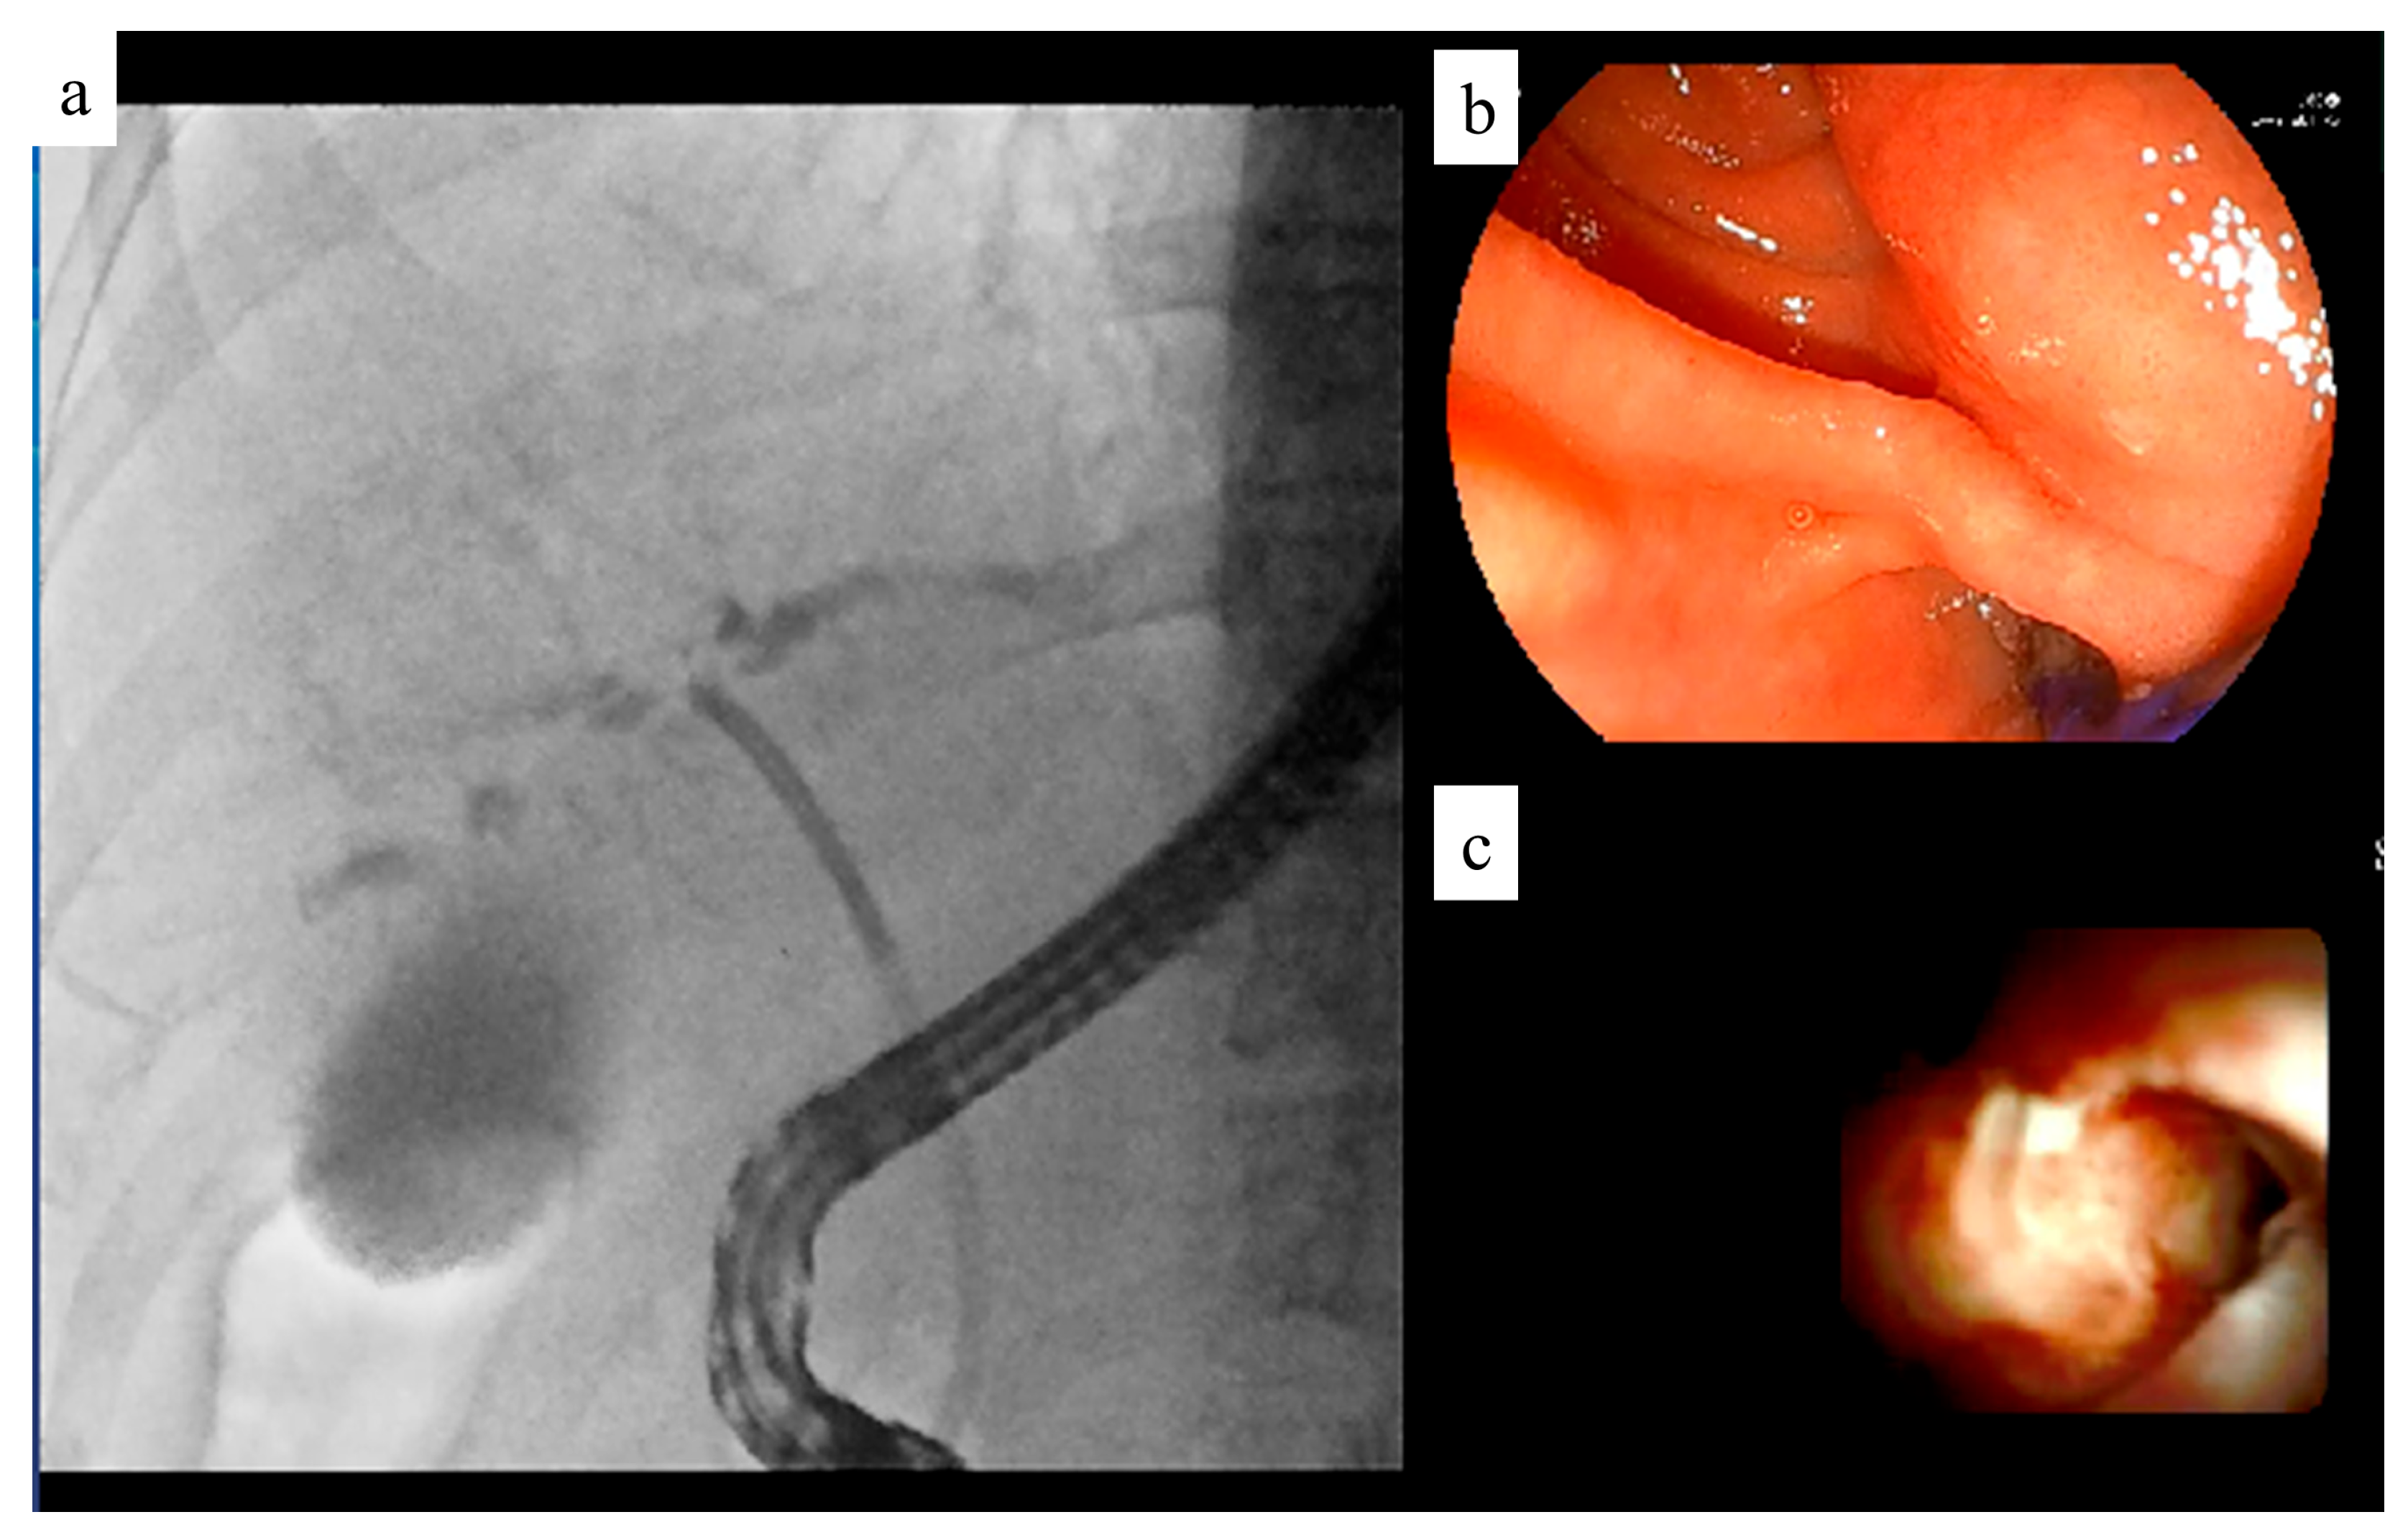

6. Recording System

Previously, fluoroscopic videos were recorded with a reduction in the number of scanning lines from 1000 to 500, resulting in lower definition. To address this, we developed the VC-1000 recording device, manufactured by Fujifilm, which maintained 1000 scanning lines for high-definition recording. The VC-1000 can record endoscopy and fluoroscopy images simultaneously.

The upgraded VC-2000, which can record up to four systems of video information simultaneously, has since been introduced (Figure 9). The VC-2000 can simultaneously record endoscopic, fluoroscopic, and EUS images as well as images from video cameras installed in the examination room. This allows the endoscopist to review the operation images after the examination. The ability to review video images recorded simultaneously facilitates communication between instructors and junior endoscopists.

Figure 9. Recording system. This system can record multiple images simultaneously. (a) Fluoroscopic image. (b) Endoscopic image. (c) Peroral cholangioscopic image.